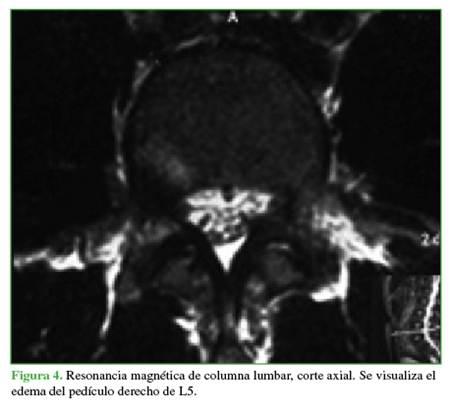

Se tomaron radiografías de columna lumbar, de frente, de perfil y oblicuas que revelaron esclerosis del pedículo derecho y espondilólisis izquierda de L5. La tomografía computarizada mostró, además de la lesión antes descrita, una solución de continuidad en el pedículo derecho, con márgenes escleróticos e hipertróficos (Figuras 1 y 2). En la resonancia magnética, se visualizó un edema en dicho pedículo lumbar (Figuras 3 y 4).

Un rasgo habitual en la pediculólisis es la esclerosis del pedículo, pero aún no resulta claro si esto representa un fenómeno de adaptación anterior a la fractura o si es una consecuencia de ella.9 Esta esclerosis unilateral le da el aspecto de vértebra anisocórica en la imagen radiológica. Sin dudas, la tomografía computarizada permite evaluar mejor el cuadro, realizar diagnósticos diferenciales, controlar la evolución y, en algunos casos, efectuar una planificación terapéutica. Las características suelen ser la presencia de solución de continuidad radiolúcida con márgenes escleróticos e hipertróficos.4 La resonancia magnética tiene una elevada sensibilidad a la hora de diagnosticar este tipo de lesiones que, si bien puede mostrar o no el trazo de fractura a nivel del pedículo, sí manifiesta el edema